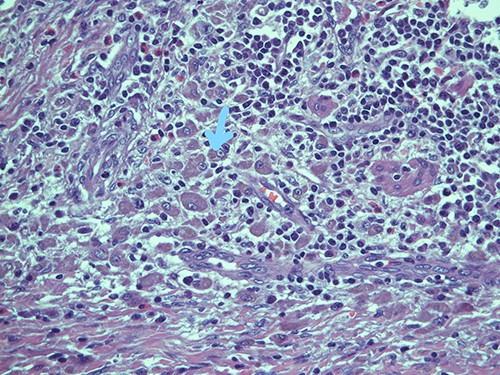

On microscopy, the appendix showed a thickening of his walls due to an accumulation of rounded elements with rich granular cytoplasm containing amorphous corpuscles and surrounded by microcalcifications, macrophage elements with adjacent de-epithelialized, ulcerated and eroded mucous tracts. No positive S100/pancytokeratin elements were found in the numerous sections examined. The morphological findings therefore indicated a form of malakoplakia (Figs 1–3), confirming its non-eptheliod and non-neoplastic nature (Fig. 4).

Submucosal cellular population is constituted by round histiocytic elements with a granular dense cytoplasm, containing typical eosinophilic bodies (arrow); haematoxylin and eosin, magnification ×20.